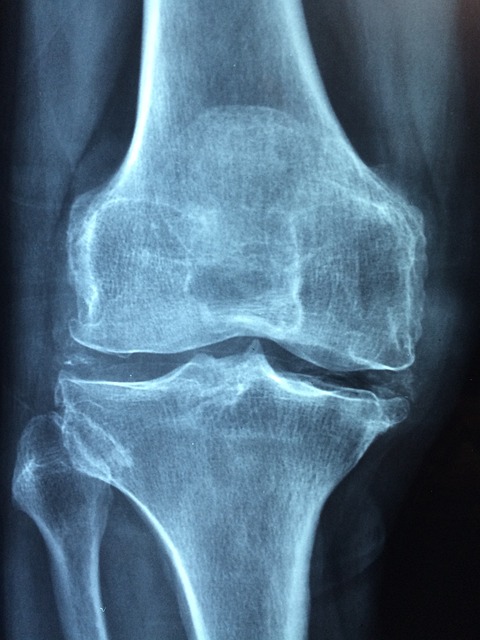

나이 40이 넘었다면 간헐적으로 나타나는 무릎 관절 통증을 무시하면 안 된다. 간단하게 엑스레이(X-ray)로 검사해도 금방 확인이 가능하니 시간이 없다고 병원에 안 가는 행동은 하지 말도록 하자.

이제 조금만 걸어도 극심한 통증으로 움직이기 조차 힘들게 된다. 무릎은 항상 부어있고, 괜찮은 날은 손에 꼽을 정도다. 병원에서 검사를 해보면 무릎뼈를 보호했던 연골조직은 어디론가 사라져 있고, 뼈와 뼈가 거의 닿아 있다.